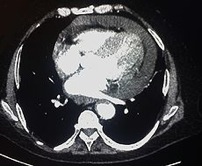

Pericardial Effusion on CT

The image below is called a CTA (CT Angiography) scan, and is created by taking a CT scan of someone after a contrast dye has been injected into their circulatory system. Notice in this scan how blood containing the contrast appears as radiopaque as bone. As you can see, the heart in this patient is surrounded by a halo of fluid. The black space seen between the heart and the effusion is pericardial fat lying on the surface of the heart.